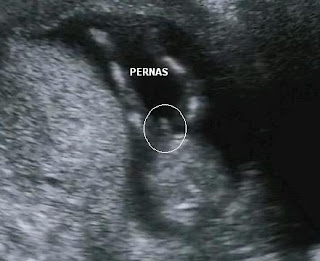

Algumas imagens foram fotografadas para ir para o prontuário junto com o laudo e o residente tirou uma foto da face do nosso filho que segue abaixo. Parece aquela ilusão de óptica em que se vê a face de Jesus J. A Helene demorou um bocado para descobrir, mas com um pouco de boa vontade é possível vê-lo.

Panhan

Fernando Akira

Jesus Cristo